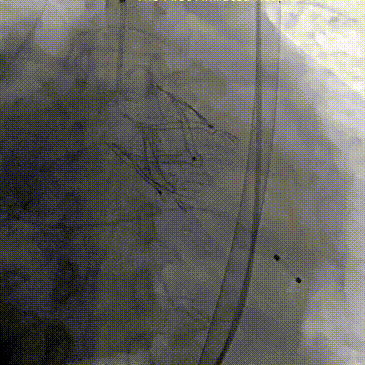

2026年伊始,TaurusTrio经导管主动脉瓣系统在复旦大学附属中山医院,浙江大学医学院附属第二医院,中国医学科学院阜外医院,首都医科大学附属北京安贞医院,四川大学华西医院等多家临床中心成功开展上市后全国首批植入。这不仅是TaurusTrio正式走向广泛临床应用的重要里程碑,更标志着中国单纯主动脉瓣反流介入治疗正式迈入了“心键合璧”的全新纪元。